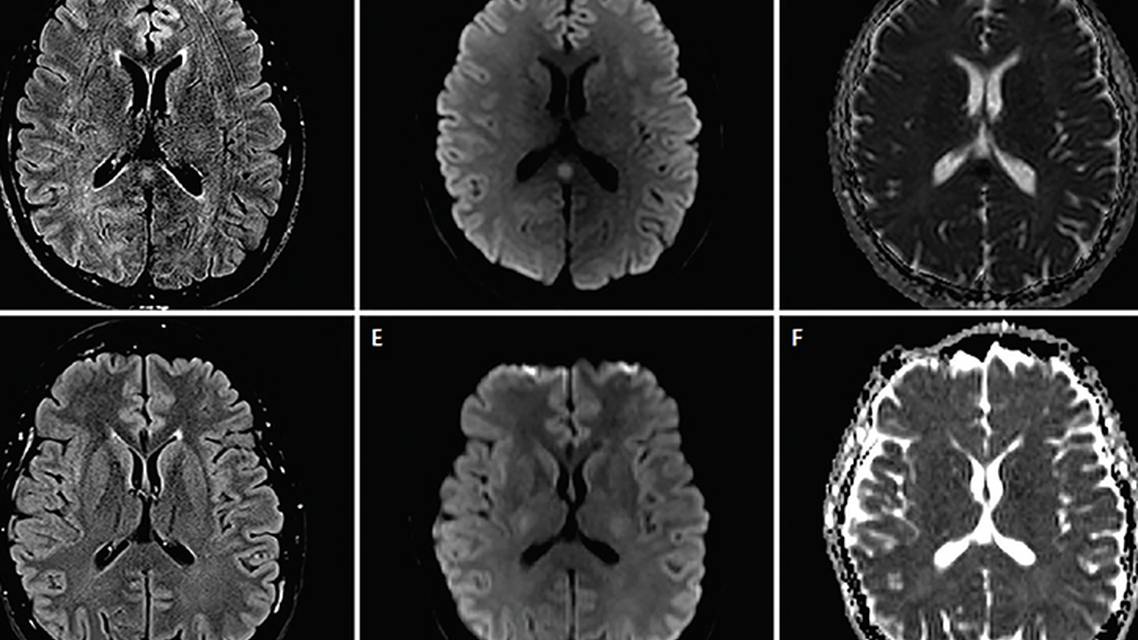

A man aged 43 years with a past medical history of recurrent sinusitis and chronic headaches since his early 20s came to the otolaryngology clinic for work-up of sinus disease. A CT scan of his sinuses without contrast incidentally showed a mass in the right cerebellopontine angle. A subsequent brain MRI with and without gadolinium revealed a right vestibular schwannoma and an abnormal hyperintense signal centered in the splenium of the corpus callosum, which showed no abnormal enhancement or diffusion abnormality (Figure 2, A-C).

Another brain MRI taken after 3 months showed no change in the nonenhancing mass-like signal abnormality throughout the corpus callosum, periventricular white matter, fornices, and mesial temporal lobes (right more than left) (Figure 2, D-F).